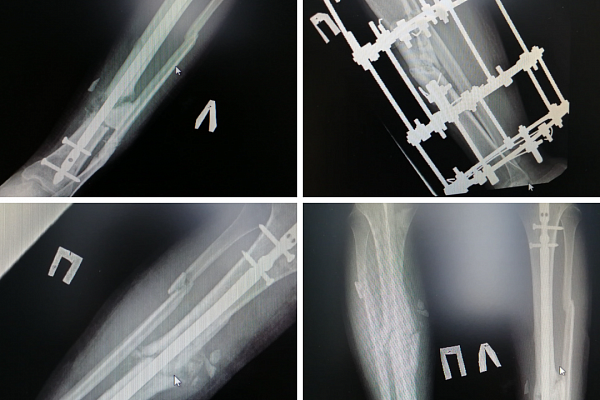

Основные хирургические вмешательства проводил травматолог-ортопед Андрей Миронов. После первой же операции одна нога практически сразу стала опорной. Даже несмотря на то, что сращения ещё не произошло, её можно было постепенно нагружать. Это важно. Без нагрузки кости становятся хрупкими, остеопорозными очень быстро. Выполнен интрамедуллярный, то есть внутрикостный, остеосинтез.

– Со второй голенью, деформация которой была более выраженной, дела обстояли сложнее. Пациенту снова наложили аппарат Илизарова, чтобы растянуть костные отломки и добиться их репозиции, – объясняет заведующий отделением ортопедо-травматологическим отделением №4 Евгений Бойко.

После того, как врачи правильно сопоставили кости, снова был применён метод интрамедуллярного остеосинтеза: в костномозговую полость погрузили штифт и зафиксировали отломки. Однако организм не принял инородное тело и отреагировал воспалительным процессом. Штифт пришлось на время убрать, заменив его антибактериальным спейсером - трубкой со специализированным костным цементом и антибиотиком. Параллельно лечили и соседние ткани, используя современные вакуумные системы. И только когда полностью справились с воспалением, остеосинтез повторили. На этот раз обошлось без нежелательных последствий.